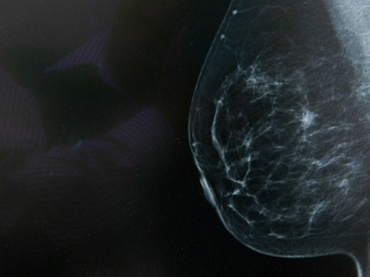

Descubren fármaco que reduce la expansión del cáncer de mama

1320505LONDRES, INGLATERRA (13/JUN/2016).- Un grupo de investigadores de Cancer Research UK descubrió un fármaco que puede reducir la expansión del tipo más agresivo de cáncer de mama, según publicó la revista Oncogene.

El compuesto conocido como JQ1 altera la reacción de las células cancerígenas ante la hipoxia o falta de oxígeno, un proceso que se encuentra presente en más del 50 % de los tumores y es más común en los cánceres de mama del tipo triple negativo, el más difícil de tratar.

Científicos de las universidades de Oxford y Nottingham (en el centro de Inglaterra) concluyeron en su estudio que el JQ1 provoca que el tejido cancerígeno deje de adaptarse a la carencia de oxígeno, lo que ralentiza su desarrollo.

El coautor de la investigación, Alan McIntyre, afirmó que «el tratamiento de la hipoxia a veces compromete el tratamiento del cáncer de mama y el JQ1 puede ser la clave para ayudar a las pacientes de esta enfermedad».

Cuando este tipo de tumor se acostumbra a los niveles bajos de oxígeno, su biología se altera y se vuele resistente a terapias comunes, razón por la que este nuevo medicamento podría cambiar la forma de combatir este cáncer, según los investigadores.

Desde Cancer Research UK, Nell Barrie, apuntó que «el estudio muestra cómo funciona este fármaco» y que «podría ser una forma de detener la expansión del cáncer», aunque remarca que ahora se debe examinar «la efectividad del JQ1 sobre los pacientes».